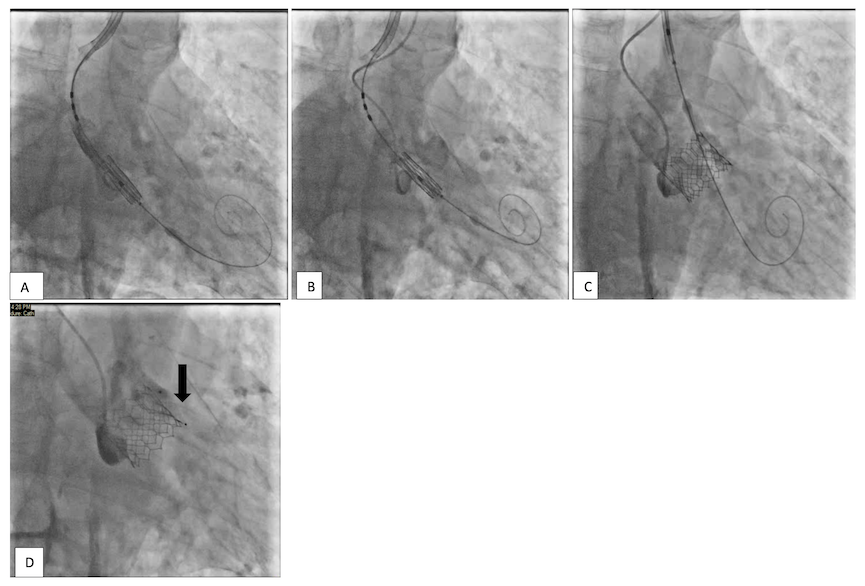

We placed a right radial artery cannula and left radial access for pigtail placement. The right axillary artery was accessed with ultrasound guidance and a 6-French (Fr) sheath was inserted. Two ProGlide sutures were deployed for pre-closure. The 6-Fr sheath was upsized to 11 Fr. The aortic valve was crossed, and a small Safari wire was placed in the left ventricle (LV). A 16-Fr Edwards eSheath was inserted over the Safari wire and positioned in the innominate artery (Figure 1A). The eSheath was partially withdrawn to create space for valve loading (Figure 1B). Once the valve was across the aortic annulus, the pusher catheter was withdrawn to the upper ascending aorta. The flex wheel of the Commander system was angled close to its maximum and the whole apparatus slowly rotated to align the Safari wire on the greater curvature of the aorta. This brought the S3 Ultra valve perfectly into annular alignment (Figure 1C). The 29 mm S3 Ultra valve was deployed in a good position at the aortic annulus, under rapid pacing through the LV wire,18 with no aortic regurgitation (Figure 1D). Vascular closure of the axillary artery was secured with the two ProGlide sutures. There were no procedural complications, and the patient went home the following day.